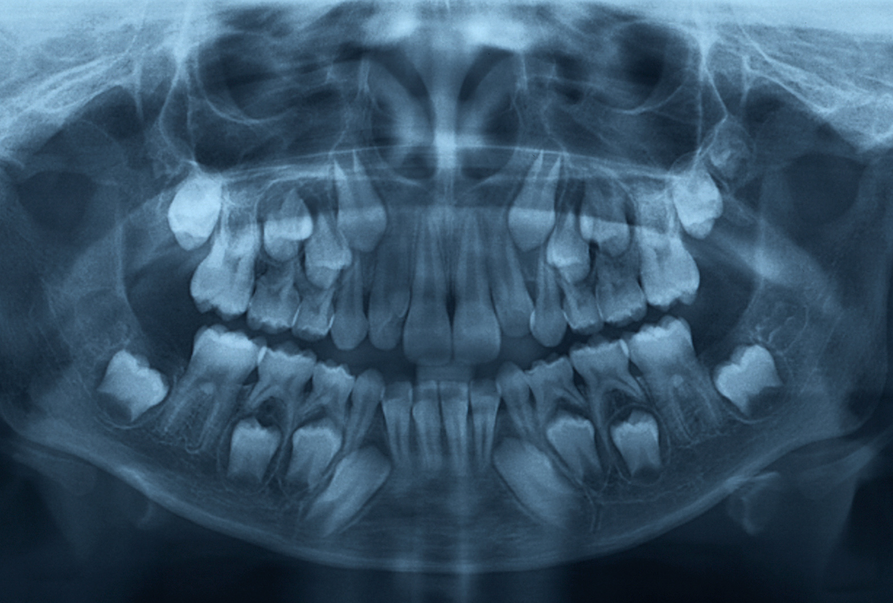

Digital X-Rays & Intraoral Imaging

Quick, low-radiation diagnostics to identify cavities, infections, and bone loss—often before they become visible to the naked eye.